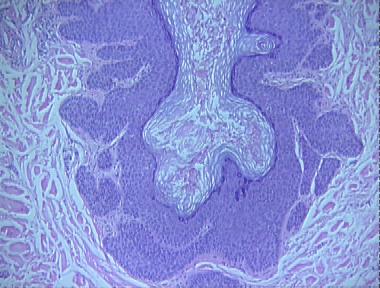

dilated pore of Winer

Histologic Features